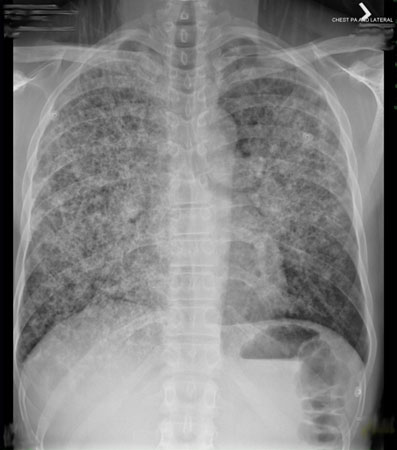

O infiltrado pulmonar persistente ocorre quando uma substância mais densa que o ar (por exemplo, pus, edema, sangue, surfactante, proteínas ou células) permanece no parênquima pulmonar. Pneumonias sem resolução ou de resolução lenta constituem as categorias comuns mais amplas de infiltrados pulmonares persistentes.[1]Menendez R, Perpina M, Torres A. Evaluation of non-resolving and progressive pneumonia. Semin Respir Infect. 2003 Jun;18(2):103-11.

A persistência é atribuída a defeitos nos mecanismos de defesa do hospedeiro, à presença de organismos incomuns ou resistentes ou a doenças que mimetizam a pneumonia.[4]Mittl RL Jr, Schwab RJ, Duchin JS, et al. Radiographic resolution of community-acquired pneumonia. Am J Respir Crit Care Med. 1994 Mar;149(3 Pt 1):630-5.

A classificação desses distúrbios pode se tornar bastante complexa, pois alguns médicos se concentram principalmente nas anormalidades radiológicas, ao passo que outros enfatizam as características clínicas associadas. A pneumonia sem resolução ou de resolução lenta é vagamente definida como uma pneumonia que não melhora clinicamente ou até mesmo piora, apesar de um mínimo de 10 dias de antibioticoterapia adequada, ou como infiltrado radiográfico que não se resolve em até 12 semanas.[6]El Solh AA, Aquilina AT, Gunen H, et al. Radiographic resolution of community-acquired bacterial pneumonia in the elderly. J Am Geriatr Soc. 2004 Feb;52(2):224-9.

A pneumonia de resolução lenta é geralmente definida como a persistência do infiltrado radiográfico em um paciente com melhora clínica por >4 semanas (<50% de resolução em 1 mês).[8]Eisenberg GM, Flippin HF, Israel HL, et al. Delayed resolution of pneumonias. Med Clin North Am. 1956 Sep;40(5):1291-303.

Uma boa resposta clínica ao infiltrado pulmonar é definida como uma eliminação de 50% dos achados radiográficos torácicos em 4 semanas de terapia.[6]El Solh AA, Aquilina AT, Gunen H, et al. Radiographic resolution of community-acquired bacterial pneumonia in the elderly. J Am Geriatr Soc. 2004 Feb;52(2):224-9.

No caso de pneumonia, a maioria dos pacientes apresenta temperatura normal e diminuição da tosse 3 a 5 dias após o início do tratamento. Quando não tiver ocorrido melhora clínica e os achados nas radiografias torácicas não apresentarem alteração ou piorarem, ou se pelo menos não ocorrer uma resolução radiográfica parcial em até 4 semanas, uma avaliação mais profunda é essencial, mesmo em pacientes assintomáticos.[2]Kuru T, Lynch JP 3rd. Non-resolving or slowly resolving pneumonia. Clin Chest Med. 1999 Sep;20(3):623-51.